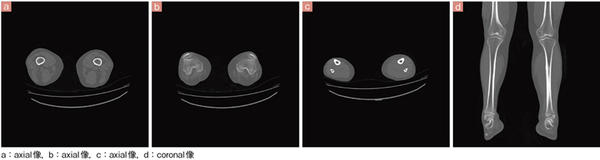

■症例3 整形領域

Aquilion PRIMEの画質については,井田係長も64列に比べ格段に向上したと評価している。「Aquilion PRIMEでは,長年マルチスライスCTを開発してきた東芝社の技術が熟成されたように思います。アーチファクトの減少や,view数が増えたことによって中心部と周辺部の画質の差がなくなり,均一性が良くなりました。例えば,整形領域での肩の撮影など,寝台の中心に位置決めできない症例でも,高画質画像を得ることができます」と述べている。